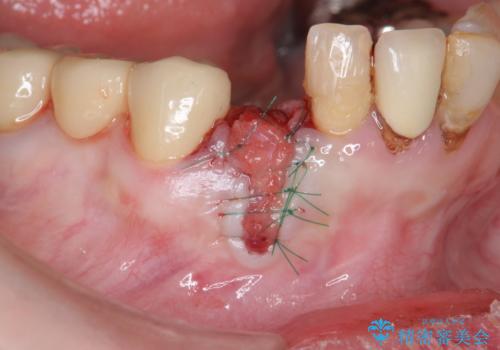

X線写真および歯周組織検査より、歯の破折 周囲骨の高度な吸収が認められました。

抜歯後、インプラントによる審美・機能改善を希望されたのでインプラント埋入に先立ち吸収した骨の再生を計画します。

歯を失う原因が虫歯や根尖病変などはなく、歯周病や歯の破折等周囲の骨を吸収する原因の場合はインプラント治療を行うに先立ち骨の造成が必要なことがあります。